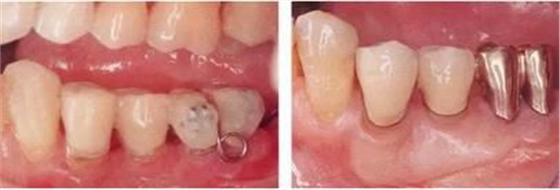

▲圖5-3,4

▲圖5-3 開(kāi)始正畸治療時(shí)的側(cè)方照。預(yù)計(jì)使左下6向遠(yuǎn)中、左下5向頰側(cè)方向移動(dòng)。

▲圖5-4 在左下4~右下3的舌側(cè)種植支抗,并用金屬網(wǎng)增加強(qiáng)度。

▲圖5-5,6

▲圖5-5 正畸治療結(jié)束后,佩戴臨時(shí)修復(fù)體以使牙列保持穩(wěn)定。

▲圖5-6 較深的牙周袋,正畸治療后留有骨組織高低差,左下6根分叉病變,附著齦不足等問(wèn)題,采取骨外科處理與FGG并用的手法進(jìn)行治療。左下6進(jìn)行牙根分割處理。